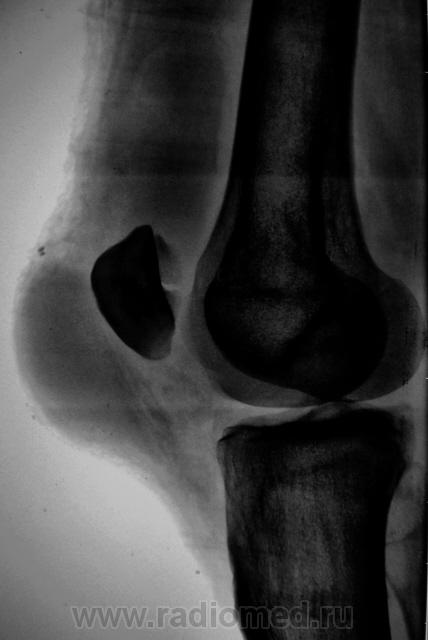

перелом надколенника( редко такой встречается) препателярная гемабурса, гемартроз, сильно пострадала суставная поверхность надколенника

Наверно все таки пателля бипартита. Представить, чтобы так красиво и ровно откололось - трудно... А мягкотканный компонент знатный...

Сам думал о "бипарцита", кстати, недавно был случай с "трипарцита". Но в данном случае был в растерянности, клиника "зашкаливает", конечно, возможно из-за мягкотканного компонента.

Кстати, на обычной рентгенограмме, произведенной в ургентных условиях "мягкотканный компонент" едва угадывается. Сильно "Сиар" спасает.

В минус травме говорит такая "красивенькая форма" отломка? НО при бипарите про мягкотканный компонент я данных ненашел..